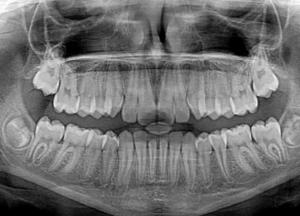

Специалисты Института рака в Нидерландах сумели обнаружить в организме человека ранее неизвестные науке слюнные железы, передает FaceNews.ua.

Голландский онколог-радиолог Воутер Фогель и его коллега, хирург Маттейс Валстар занимались изучением передовой технологии сканирования в рамках проводимого исследования. Ученые пытались разобраться в том, какие негативные побочные эффекты радиационное излучение способно оказывать на область шеи и головы. Именно в процессе испытания новых методик они обнаружили, что в задней зоне носоглотки засвечиваются две загадочные области, напоминающие неизвестные прежде слюнные железы. Впоследствии специалисты выделили найденные железы, воспользовавшись специальным маркером, чтобы не повредить их в процессе лечения с применением лучевой терапии.

Эта новость может быть весьма позитивной для пациентов, которые страдают опухолями в указанных частях тела, поскольку теперь радиологи смогут обходить указанную область и исключить риск осложнений. В скором времени будут проведены соответствующие исследования в сфере онкологии и проведения лучевой терапии.